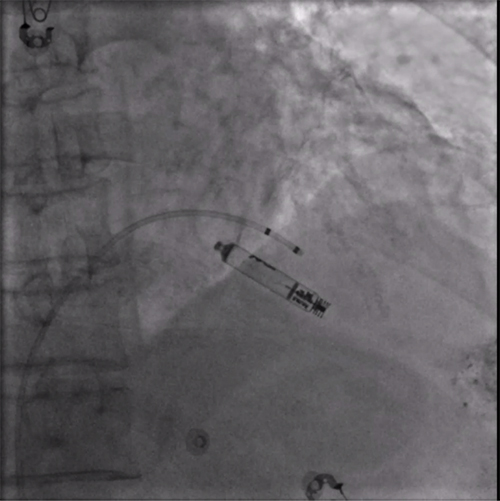

经过周密的术前准备,彭晖、孙志军两位主任带领邸北冰主治医师、柳晓娜主治医师和梁立丰医师在内的起搏电生理团队,于心脏介入手术室为患者实施手术。手术团队股静脉穿刺成功后,首先对下腔静脉进行造影并将外鞘放置送入下腔静脉,随后将新型主动固定螺旋无导线起搏器顺利跨瓣送入右心室目标位置,旋入前测试无导线起搏器各项电学参数良好,确认位置合适后旋入固定起搏器,在植入过程中动态测试起搏器各项参数以辅助判断固定程度,达到标准后进入对接栓模式,再次测试起搏器固定位置稳定、各项参数良好后释放起搏器,最后撤出鞘管,顺利完成手术。整个手术流程高效有序,医疗团队成员紧密配合,默契无间,仅耗时40分钟共同完成了这一具有挑战性的任务。

电学标测参数良好,在此旋入1.5圈后进入对接栓模式,

摇摆与电学参数测试后释放起搏器

植入后右前斜

植入后左前斜